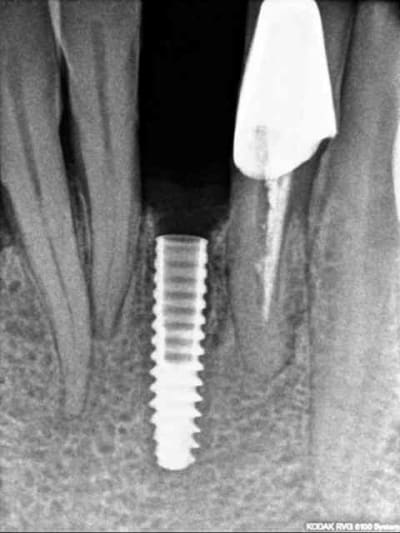

1) j+8 jours

2) radio de contrôle

c'est promis je vous posterai la couronne une fois terminée.

encore trois mois d'attente...